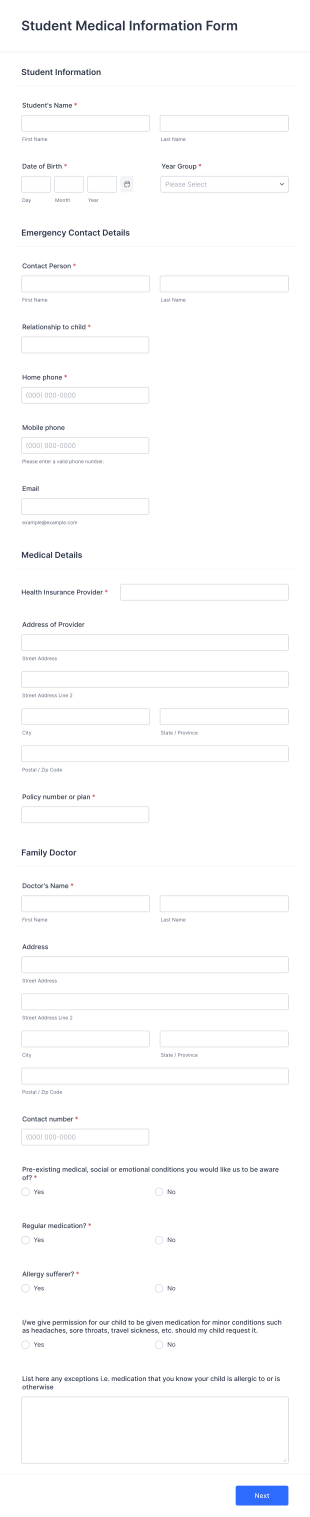

Student Medical Information Form

A student medical information form stores and organizes a student’s medical information and assessments in one place.